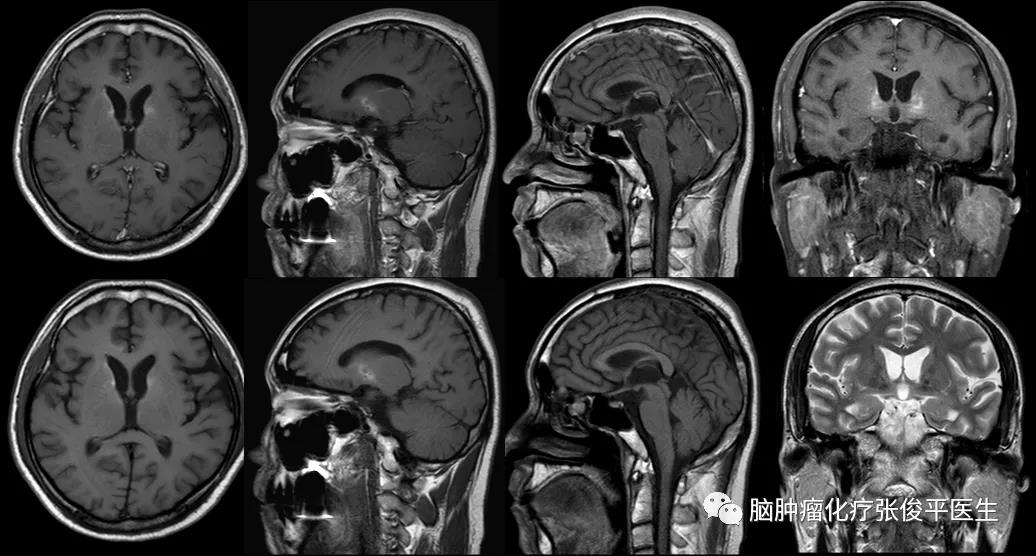

患者,男性,44岁。2009年7月3日,患者在饮酒后出现左侧口角歪斜,不伴有恶心呕吐,不伴有意识丧失,无肢体抽搐等,在当地医院按“中风”给予中医针灸治疗,症状好...